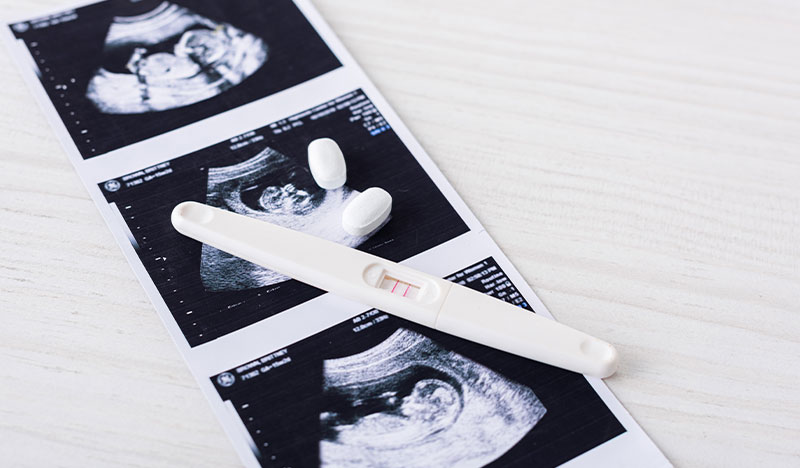

ބައިގެން ދިޔުމަކީ މާބަނޑުވެ 20 ވަނަ ހަފުތާގައި އާންމުކޮށް ވާ ކަމެކެވެ. މިއީ ދެވަނަ ޓްރައިމިސްޓާގެ މެދުތެރޭގައި ވާ ކަމެކެވެ. ބައެއް ފަހަރު މާބަނޑުދުވަސްވަރު އަވަހަށް ދަރިމައިވުން ނުވަތަ ބަނޑުގައި ރިއްސުން ފަދަ ކަމެއް ކުރިމަތިވަނީ 13 ހަފްތާގެ ކުރިންނެވެ. ނަމަވެސް ގިނަ ފަހަރު 10 ހަފްތާގެ ކުރިން ބަނޑުގައި ރިއްސުމަކީ ދިމާވެދާނެ ކަމެކެވެ.

ބަނޑުގައި ރިއްސުމަކީ އާންމު ކަމެކެވެ. 10 ޕަސެންޓާއި އާއި 20 ޕަސެންޓާއި ދެމެދުގެ އަދަދަކަށް މާބަނޑުދުވަސްވަރު ދަރިމައިވުން ނިމުމަކަށް އާދެއެވެ. މާބަނޑުދުވަސްވަރު ބައުގެން ދަނީ ފުރަތަމަ ތިންމަސްދުވަސްތެރޭގައެވެ. ގާތްގަނޑަކަށް 80 ޕަސެންޓު މީހުންނަށް މިގޮތަށް ދިމާވެ އެވެ.

ނަމަވެސް އެއްވެސް އަލާމާތެއް ނެތި ބަނޑުގައި ރިއްސުމަކީ އެކަށީގެންވާ ކަމެކެވެ. މެމޯރިއަލް ހެލްތުކެއާ ސިސްޓަމްގެ މައިނާރު ފީޓަލް މެޑިސިން ޕްރޮގްރާމްގެ އެމްޑީ، އޯބީ-ޖީއައިއެން އަދި މެޑިކަލް ޑިރެކްޓަރު ލޯރީ ސްކޮޓް ވިދާޅުވީ މިއިން އަލާމާތެއް ނުފެނި ބަނޑުގައި ރިއްސާނަމަ ޑޮކްޓަރު އަލްޓްރާ ސައުންޑް ހެދުން މުހިންމުވާނެ ކަމަށެވެ. ސަބަބެއް ކަމަށް ވިދާޅުވީ ނޭނގި ބައިގެންދިޔުމުގެ ފުރުސަތު އޮވެދާނެތީ ކަމަށެވެ.